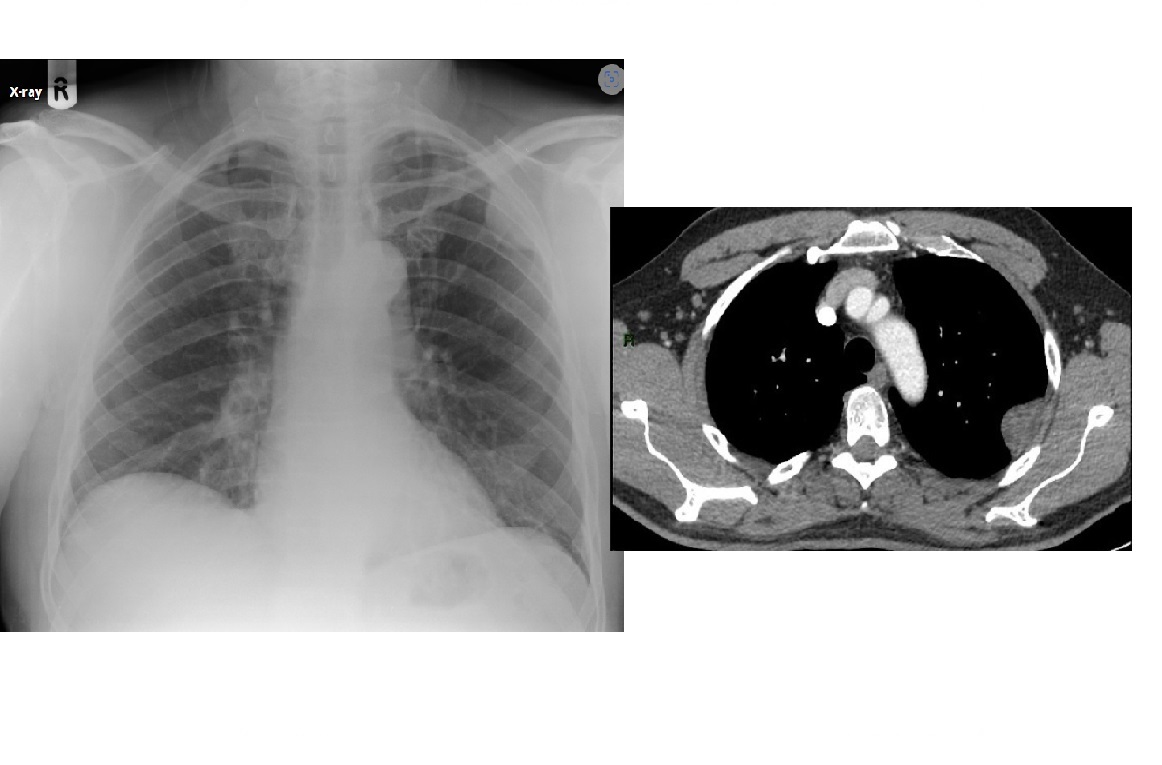

Septic emboli

Peripheral wedges shaped densities +/- cavity

Lower lobe predominant